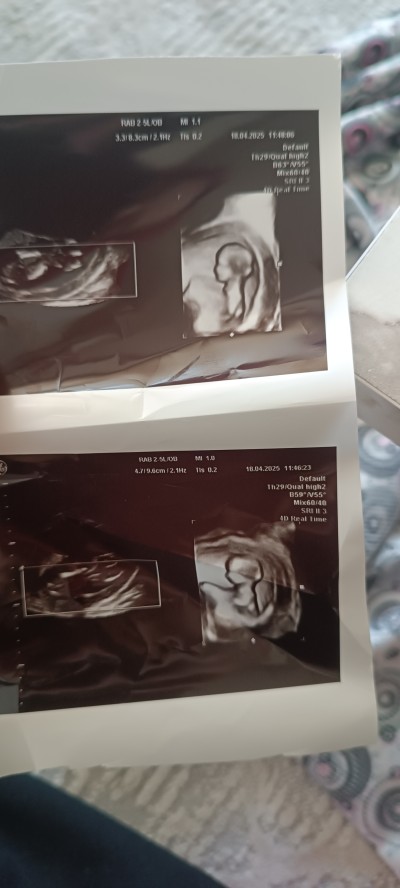

13.hafta  tahminlerinizi alayım

Gebelik haftası 13+1

Erkek canım bacak arasında yanlış değilsem pipisi görünüyor 😀 sağlıklı olsun

Sonucu öğrendim ve Kız